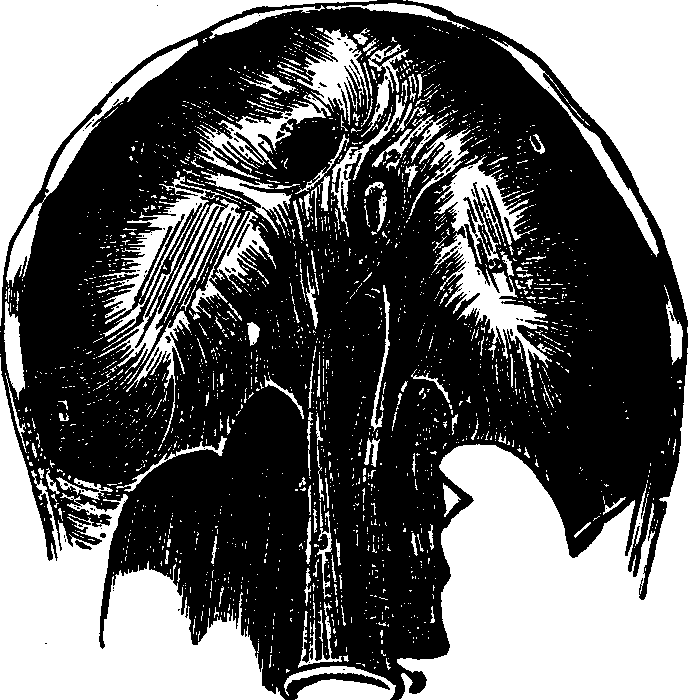

Fig. 38. Red corpuscles of human blood, represented at

a, as they are seen when rather beyond the focus of the

microscope; and at b as they appear when, within the focus.

Magnified 400 diameters.

Fig. 39.

Development of human lymph and chyle-corpuscles into red corpuscles of

blood. A. A lymph, or white blood-corpuscle. B. The same in

process of conversion into a red corpuscle. C. A lymph-corpuscle

with the cell-wall raised up around it by the action of water. D. A

lymph-corpuscle, from which the granules have almost disappeared. E.

A lymph-corpuscle, acquiring color; a single granule, like a nucleus,

remains. F. A red corpuscle fully developed.